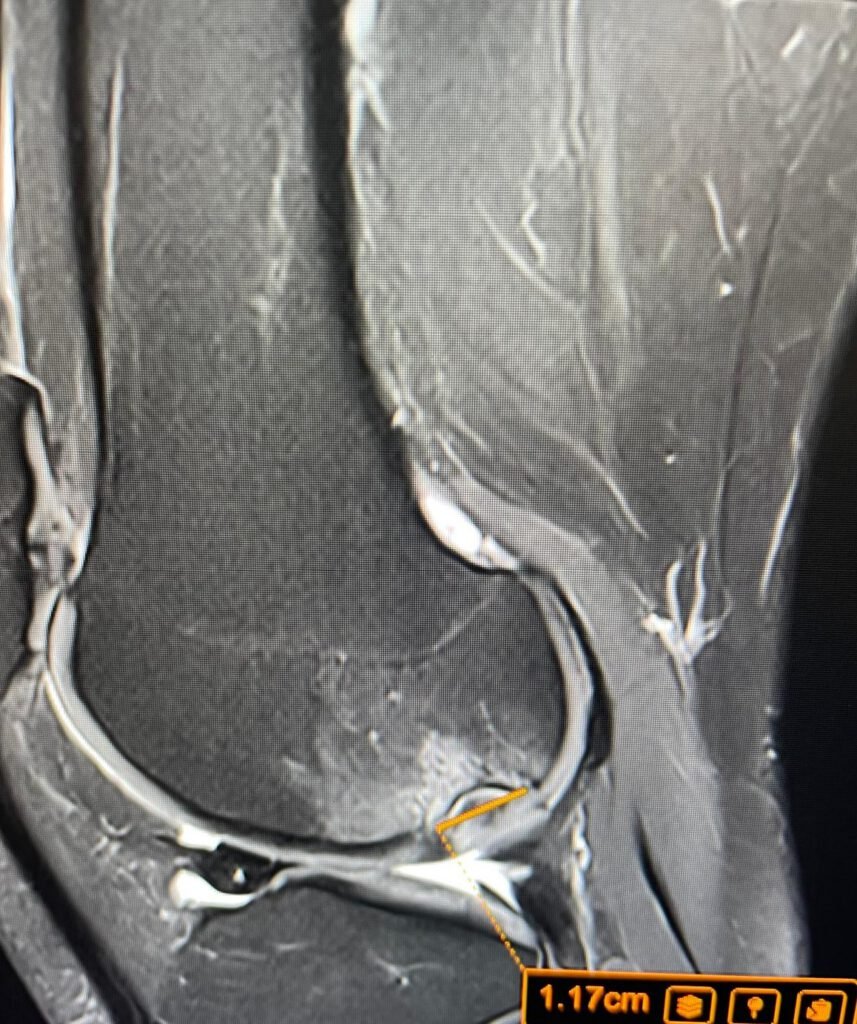

When the patient came to LSRI and underwent an urgent MRI, Dr Prashant Sankaye’s review of the images clearly revealed advanced Osteochondritis Dissecans (OCD) — a condition where a segment of cartilage and underlying bone separates from the joint surface due to insufficient blood supply. Standard X-rays had been reported as normal by his GP. Because standard X-rays cannot reliably detect OCD in its early stages, advanced imaging is the gold standard for assessing this type of condition.